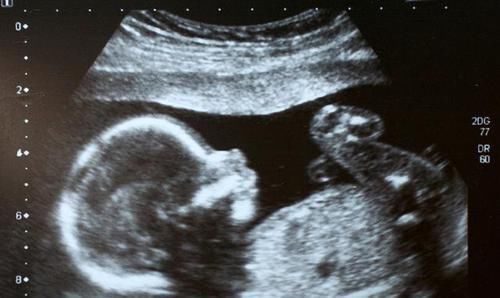

别看现在B超使用率很高,感觉技术相当成熟的样子,其实行内人都知道,它的问题极多,比如最关键的一条:成像模糊。

B超的工作原理是声波与光波技术结合而成,通过特殊的算法,将这些检测手段反馈的数据进行分析,最后形成图形供给医生诊断。